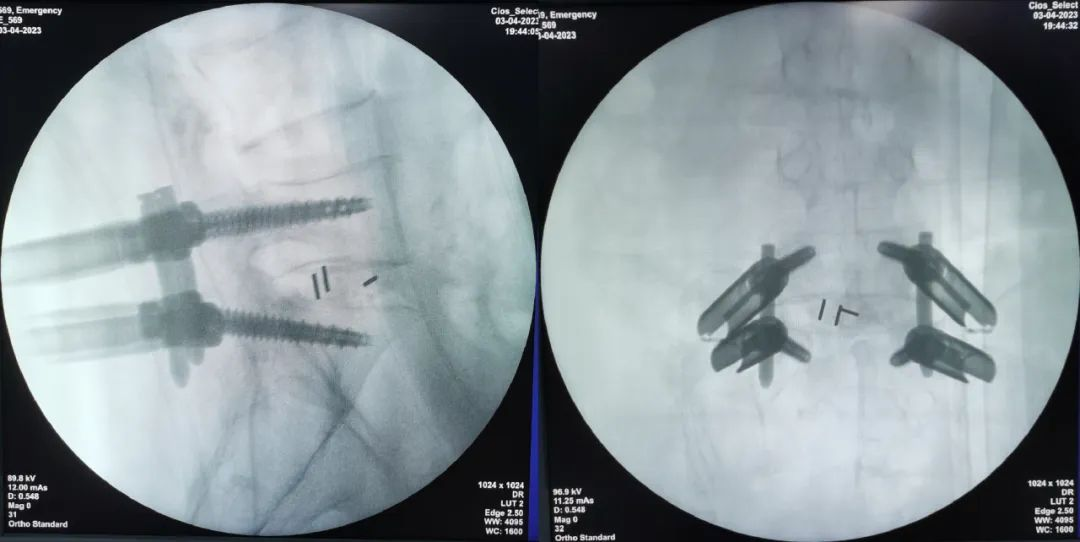

术中透视

术日,在精准的皮肤切口定位后,置入双侧通道内镜,内镜下见巨大椎间盘突出、椎管狭窄严重,在陈子华主任指导下,脊柱外科微创团队规范、仔细操作,摘除巨大椎间盘组织后,植入椎间融合器及椎弓根螺钉。术中椎管内减压充分、椎间盘组织去除彻底、脊柱系统得到稳妥固定。术后患者自觉下肢麻痛症状即刻改善,术后第二天,患者在主管医生指导下,佩戴腰围下床活动,状态良好。